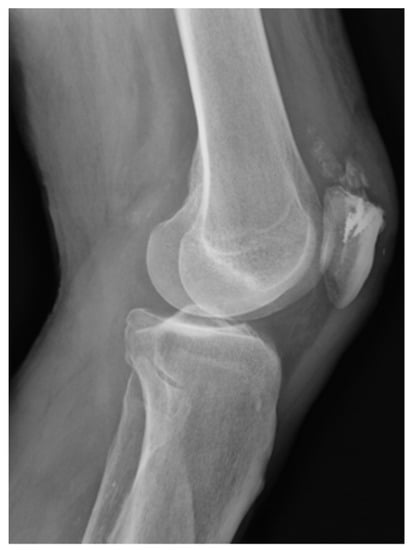

Thirty-three patients (41 implants) underwent operative intervention with procedures that required the implantation of a suture anchor. Of the 33 patients, 27 had one implant (27 implants), five had two implants (10 implants), and one had four implants (Figure 1).

Figure 1. Quadriceps reconstruction after its rupture by mean of 4 TWINFIX.